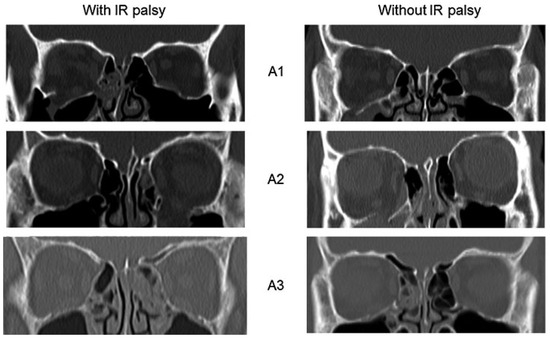

| Fracture extent, n (%) | |||

| A1 | 2 (40.0%) | 16 (37.2%) | 0.52 |

| A2 | 2 (40.0%) | 13 (30.2%) | 0.47 |

| A3 | 1 (20.0%) | 14 (32.6%) | 0.55 |

| Fracture area, mean ± SD, cm2 | 1.8 ± 0.7 | 0.7 ± 0.2 | 0.01 |